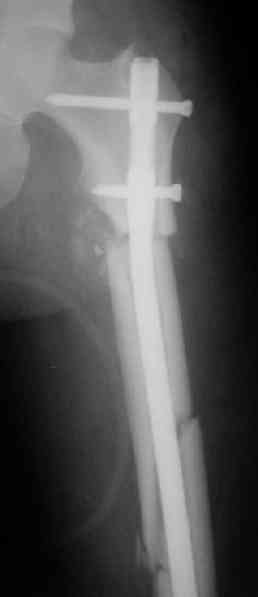

Судя по уровню перелома, винты в шейку избыточны, подойдет и диафизарный гвоздь. Все, что нужно, это тиски и труба. Загнуть сразу ниже отверстий градусов на 8-10, и вся недолга. Последние годы у нас это рутинная практика. Предызогнутые еще с завода гвозди неудобны тем, что они уже правый-левый.

Согласен, что закрытый реостеосинтез с рассверливанием и коррекцией оси - это то, что надо. Мы бы ввели в центральный отломок статических 2-3 винта, и один динамический винт в дистальном отломке.

Вот несколько. С тисками и трубой на днях сделаем.